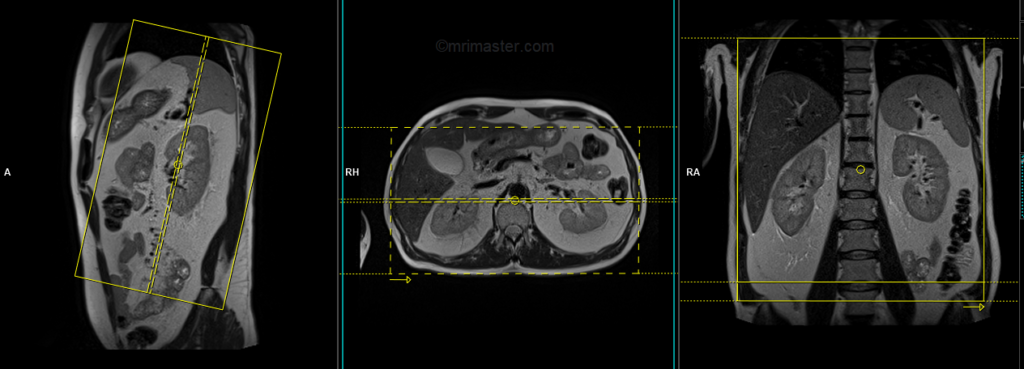

T2 tse breath hold (HASTE) coronal 3mm

Plan the coronal slices on the axial plane; angle the positioning block parallel to the midline along the right and left kidneys. Check the positioning block in the other two planes. An appropriate angle must be given in the sagittal plane, parallel to the long axis of the kidney. Slices must be sufficient to cover both kidneys anterior to posterior. Phase oversampling and, in the case of 3D blocks, slice oversampling, must be used to avoid wraparound artifacts. Instruct the patient to hold their breath during image acquisition. In our department, we instruct the patients to breathe in and out twice before the “breathe in and hold” instruction.

Parameters

| TR 5000-6000 | TE 150 | FLIP 150 | NXA 1 | SLICE 3MM | MATRIX 256×256 | FOV 300 | PHASE R>L | OVERSAMPLE 50% | IPAT ON |